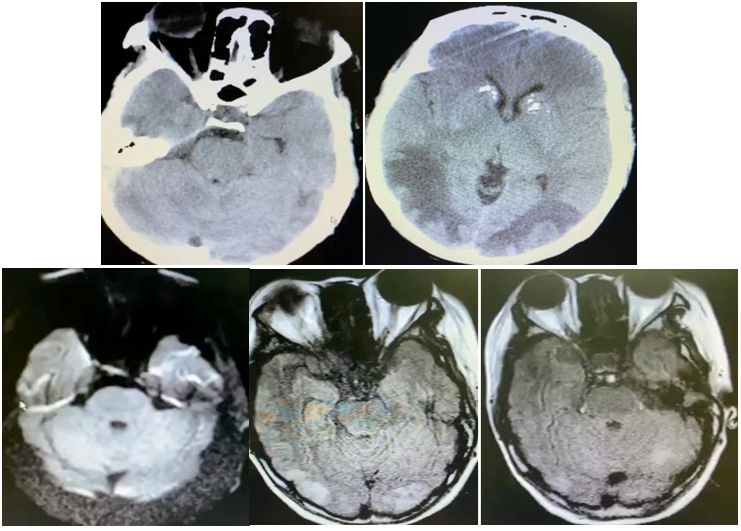

女性,75岁,发作性抽搐半月,意识障碍2天。

答案:抗GABABR抗体相关脑炎。抗GABABR抗体相关脑炎在临床上符合边缘性脑炎的表现,通常以癫痫发作、记忆力减退和意识障碍为主要特征。表现形式多样的癫痫发作是早期最突出的特征,多为继发性全身发作,还可以表现为复杂部分性发作、全面发作、全面强直-阵挛性发作、部分性运动性发作,甚至出现癫痫持续状态。患者多合并有记忆力减退和意识障碍,病程后期甚至出现幻觉和人格改变。癫痫发作也可以作为其唯一的表现。约有50%的GABABR抗体阳性患者合并小细胞肺癌,少数可合并其他肺部神经内分泌肿瘤、黑色素瘤及良性胸腺瘤等肿瘤。头MRI一侧或两侧内侧颞叶FLAIR/T2像信号增高提示该诊断的可能,但是这也见于其他自身免疫性脑炎。